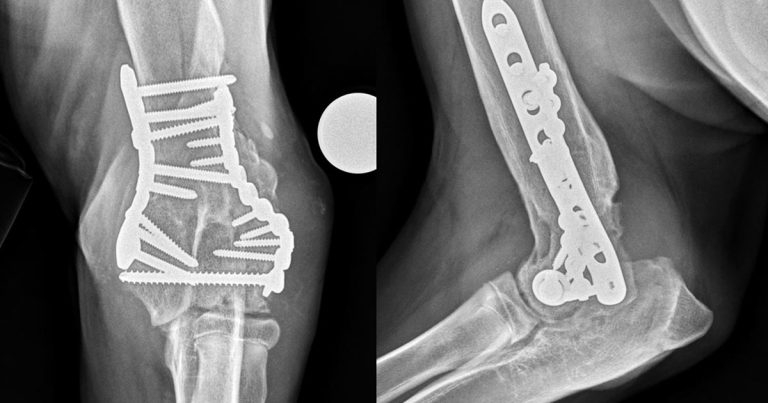

Post-traumatic OA is relatively common in dogs where it may occur secondary to ligamentous damage and resultant instability (Henrotin et al, 2005), or as a result of articular fracture (Marcellin-Little et al, 1994; Figure 2). Additionally, albeit less commonly, inflammatory (infectious or immune-mediated) and metabolic conditions can result in secondary OA.